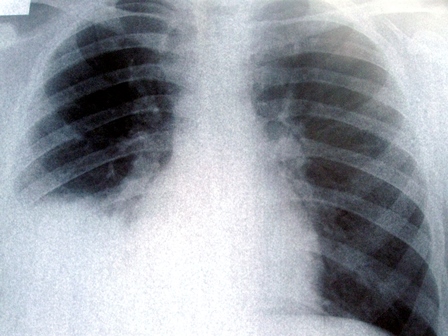

יורשיו של בעל עסק לצביעת מכוניות שנפטר מסרטן ריאות טענו שהמחלה נגרמה בשל תנאי עבודתו. לעומתם, ביטוח לאומי טען שהמנוח לקה במחלה עקב עישון כבד. בתחילת השבוע בית הדין לעבודה קיבל את טענת היורשים.

במשך למעלה מ-40 שנה עבד המנוח בעסק לצביעת מכוניות שפתח יחד עם אשתו. במסגרת העבודה, נחשף האיש לחומרי הריסוס באופן תדיר - מספר שעות בכל יום, חמישה ימים בשבוע.

לפני שש שנים גילה המנוח שהוא חולה בסרטן ריאות, וביקש מביטוח לאומי להכיר בו כנפגע עבודה על פי עיקרון המיקרו-טראומה. אלא שביטוח לאומי דחה את בקשתו והשיב לו שמחלתו היא "מחלה טבעית", מה גם שהוא מעשן כבד.

מומחה רפואי שמונה בהסכמת הצדדים ציין כי עישון הוא גורם הסיכון העיקרי לסרטן הריאות, והמנוח היה מעשן כבד במשך עשרות שנים, אך עם זאת, גם תנאי העבודה שלו היוו סיכון למחלה ולדעתו אף השפיעו משמעותית על בריאותו.

לגופו של עניין, השופט הסביר כי כדי להכיר בפגיעה בעבודה על פי תורת המיקרו-טראומה, יש להוכיח שתנאי העבודה גרמו למחלה הנטענת בשיעור של לפחות 20%. במקרה זה, המומחה ייחס לתנאי עבודתו של המנוח "השפעה משמעותית" בשיעור של 33%.